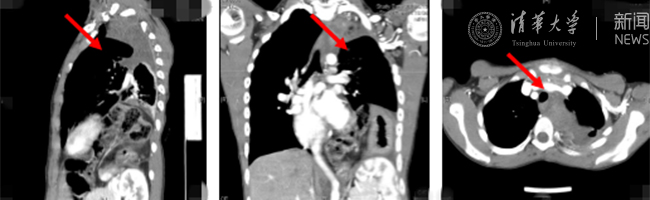

开云新闻网8月30日电(通讯员 杨峰)如图中所示,本是正常人心脏、左肺的位置,被发于神经鞘的巨大肿瘤占据,导致一位刚满12岁的男孩胸痛、咳嗽、呼吸困难。近日,北京开云长庚医院神经外科与胸外科联手,由神经外科王贵怀主任主刀,成功为男孩切除胸腔巨大神经鞘肿瘤。

患者胸腔内巨大的肿瘤。

半年前,患者经常会出现胸痛、咳嗽和呼吸困难,在当地医院检查发现左侧胸腔巨大占位,左肺及心脏明显受压。王贵怀大夫接诊,仔细查体了解病情,并反复认真阅片后,认为左侧胸腔巨大肿瘤来自于胸椎椎管内,神经鞘瘤可能性大。该肿瘤体积巨大,占据绝大部分胸腔空间,压迫左肺、纵隔大血管及膈肌。